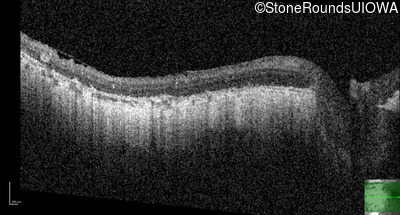

OD OS

Age at visit: 33 years